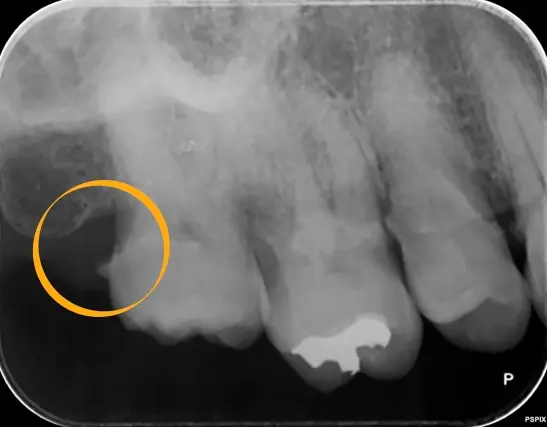

一方、縁下歯石は歯ぐきの中、歯周ポケットの奥にできる歯石です。血液成分が混ざるため黒褐色をしており、目で見ることはほとんどできません。そのため、ご自身では気づきにくいのが特徴です。

しかし実際には、この縁下歯石こそが歯周病を進行させる大きな原因となります。歯ぐきの奥で細菌が増殖し、炎症を慢性的に引き起こしてしまうのです。

↑ ⚪︎で囲っているところに縁下歯石がついています。